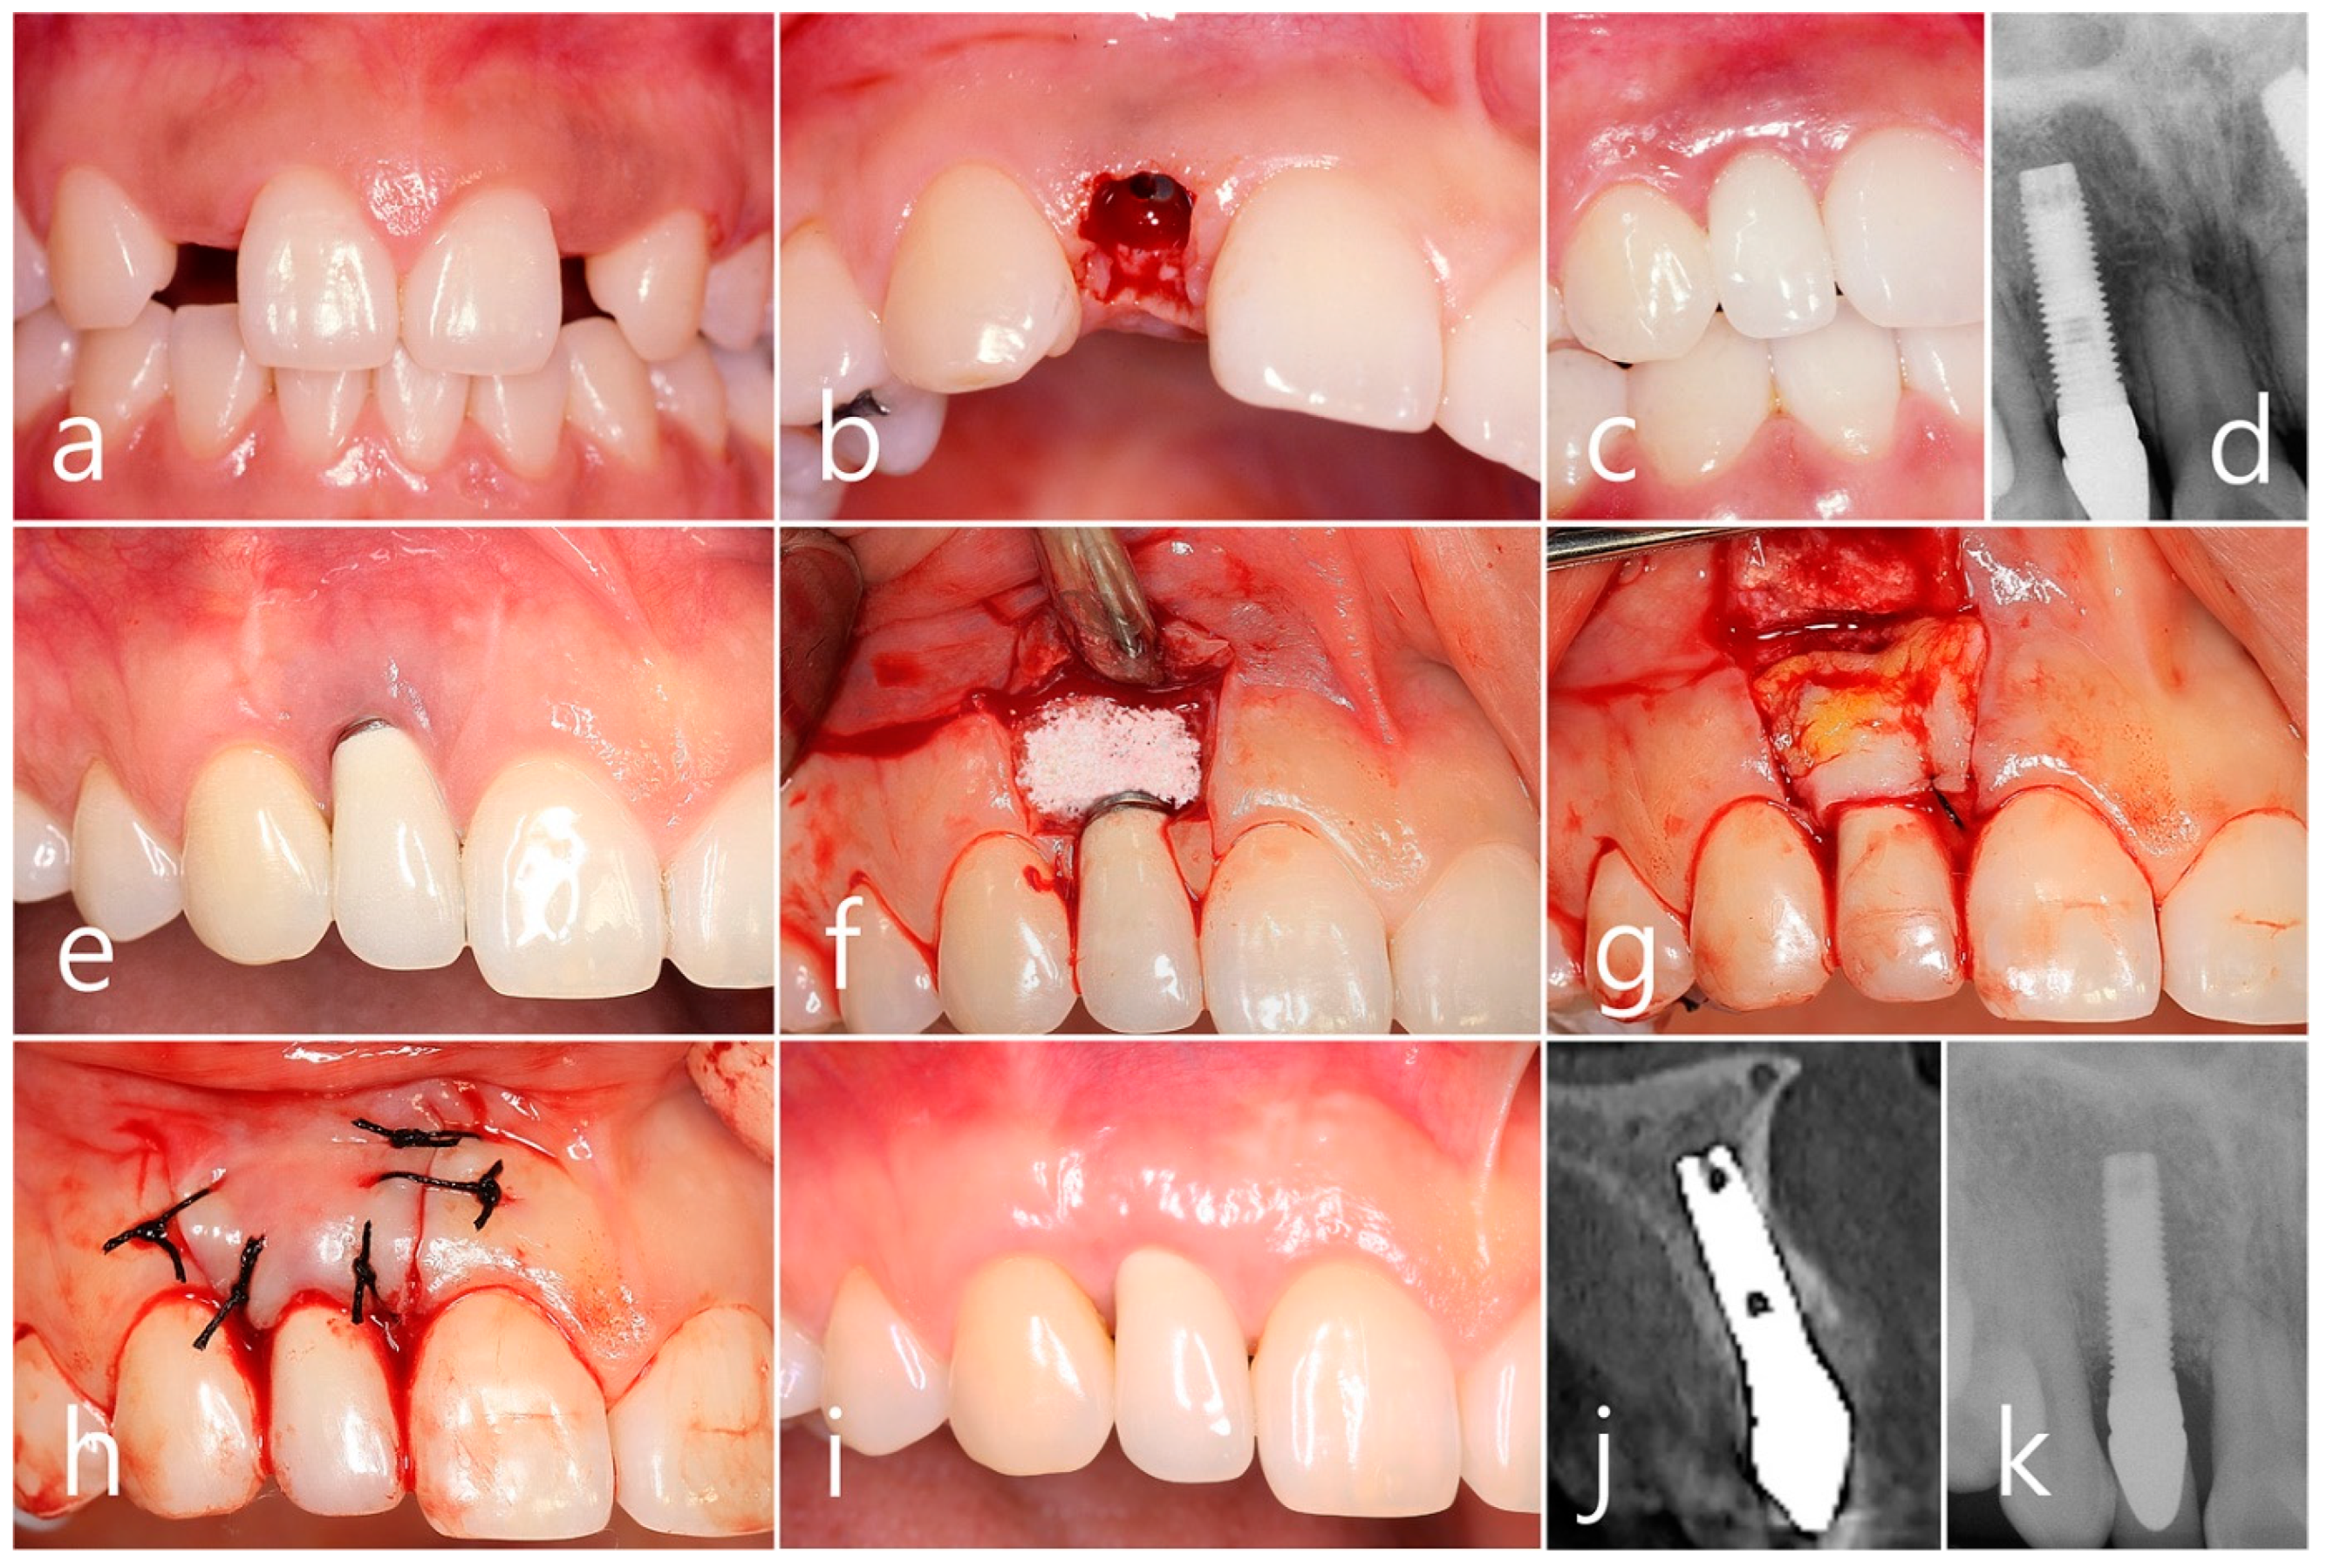

2.1. Case 1